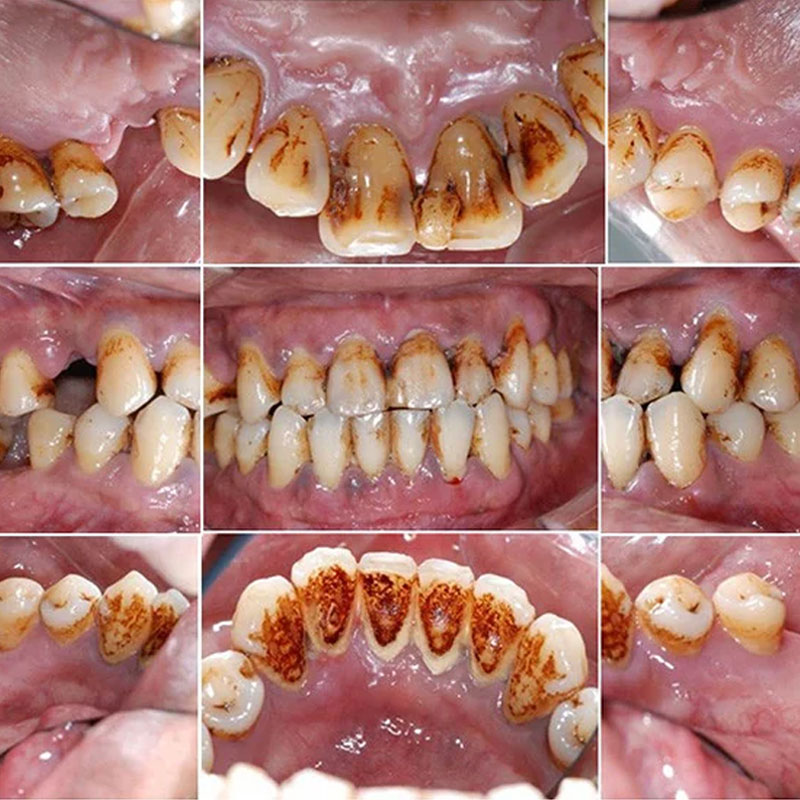

全口牙周治療

日期 : 106年7月11日